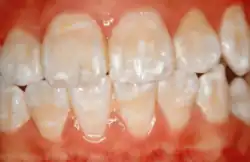

Enamel hypocalcification

Enamel is the outermost layer of the tooth which serves as a protective layer from physical, thermal, and chemical damage. Ameloblasts are the cells that produce the enamel. Their life cycle, known as amelogenesis, is divided into six stages: morphogenetic, organizing, formative, maturative, protective, and desmolytic. Enamel mineralization occurs during the maturation stage. Hence, defects in the maturation stage result in hypocalcification or hypomineralization.[1] Enamel hypocalcification is the inadequate deposition of inorganic ions, resulting in the appearance of translucency, white-chalky spots, and yellow-brown discoloration on the surface of the tooth associated with increased sensitivity and a higher risk of developing dental caries.[2]

Enamel hypocalcification is characterized by the presence of white spots or streaks on the teeth due to reduced mineral content,[34] posing both cosmetic concerns and potential structural weaknesses. White spots can also be seen in patients. As the enamel undergoes demineralization, it becomes thinner, often leading to yellow or brown discoloration. The severity of this discoloration can range from mild yellowing to more pronounced brown staining, reflecting the extent of enamel loss.[7] This compromised enamel layer can also heighten tooth sensitivity to temperature changes and sugary foods, as external stimuli more easily reach the pulp, causing discomfort. Additionally, individuals with enamel hypocalcification experience a higher incidence of dental caries, as the weakened enamel provides less resistance to acid produced by oral bacteria.[19]

Clinical manifestations

Enamel hypocalcification is characterized by visible defects in the enamel, often manifesting as white spot lesions or brown discolorations.[35] In cases such as dental fluorosis, this may include mottled patterns on the enamel surface which vary in appearance and extent based on the severity of the condition.[36] In advanced cases, the mottled appearance of the enamel can expose the underlying dentin, creating an uneven and sometimes porous surface. Though the matrix of the enamel initially forms to a typical thickness, the mineralization or calcification process is incomplete or deficient, leading to softer and structurally compromised enamel.[35]

This compromised enamel is more susceptible to staining due to its rougher surface texture and increased permeability, which allows pigments and external elements to penetrate more easily. The weakened enamel may begin to wear away, especially on the occlusal surfaces of the molars, where mechanical forces are most intense. In some individuals affected by severe enamel hypocalcification, the structural deficiencies also contribute to anterior open bite where the upper and lower front teeth do not meet when biting down. This malocclusion can further complicate both functional and aesthetic aspects of the dentition.[37]